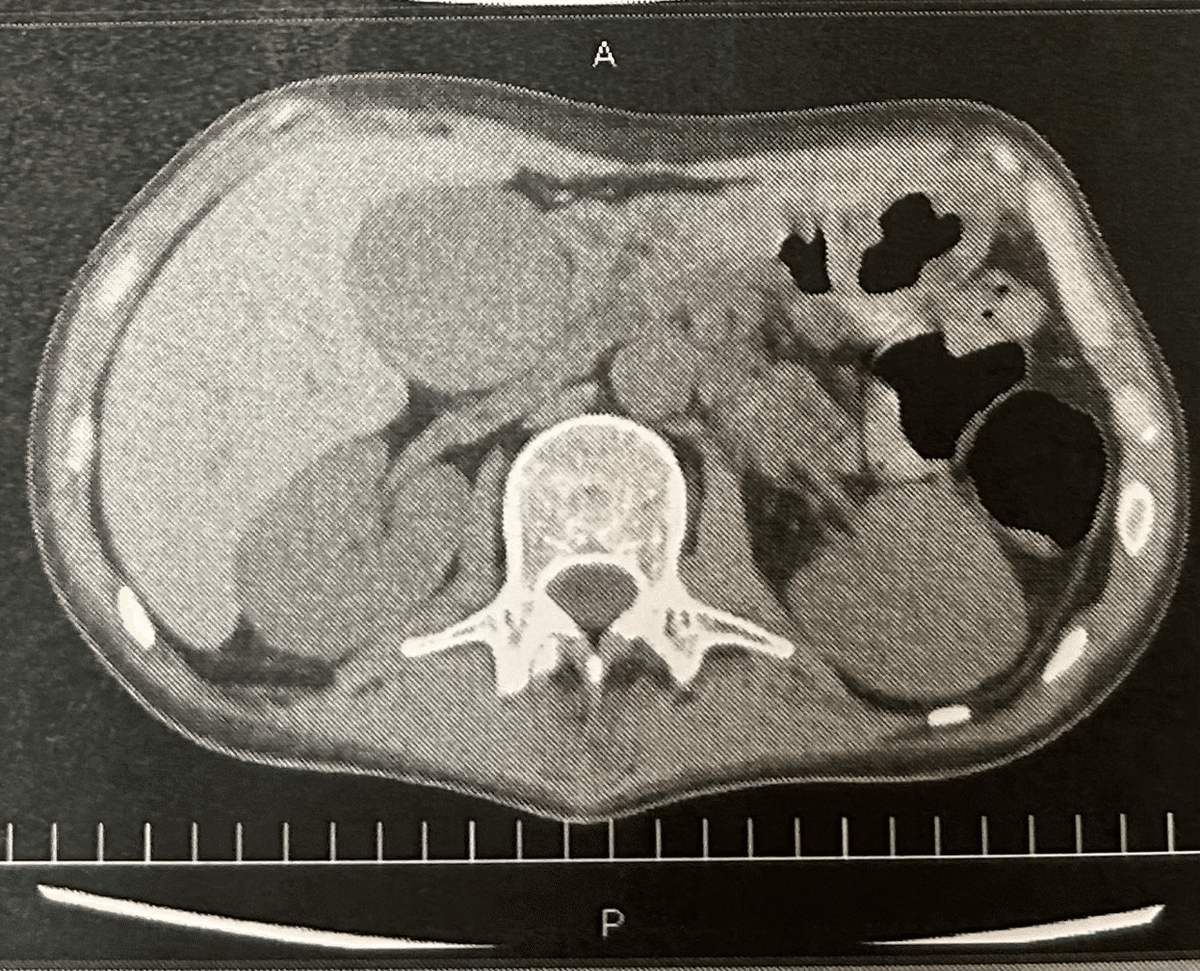

私の元々あった体重は58kgから39kgまで減っていました。そして、ずっと動けなかったため腰には褥瘡が出来てしまいました。褥瘡とは長い期間同じ体勢でいる事で、血行が悪くなり皮膚が壊死してしまい腰の骨が見えてしまう症状です。また、肝臓に障害を受けた事で腹水が溜まり、お腹はまるで妊婦さんのようになってしまいました。

ただ、2024年11月に入ると再び肝臓の値が悪くなりました。お腹が痛くなり、再び嘔吐を繰り返すようになったのです。私と両親はまた拒絶反応が出たのではないかと不安になりました。そして、検査の結果は胆石による急性胆嚢炎でした。これは拒絶反応とは関係なく、偶発的に起こったものらしく、手術が必要となりました。

一般的には簡単な手術なのですが、移植を終えたばかりの私の体はこれに耐えれるかわからないという事もあり、大量の輸血をしながら手術を行いました。私は最後の試練だと思い、手術室に向かったのを覚えています。

結果は無事に成功、肝臓の値も改善していきました。お腹に傷は残りましたが勲章として逆に誇らしい気持ちになりました。